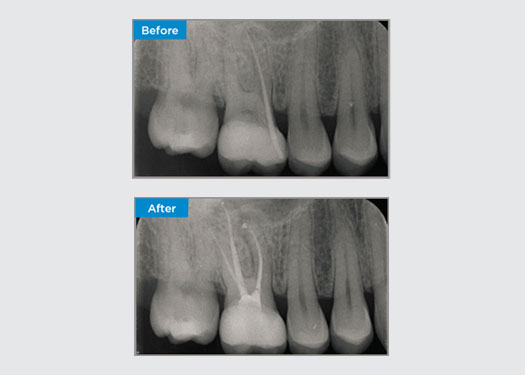

A 35 year old female patient presented after referral from a Specialist Periodontist. During the initial endodontic assessment the patient mentioned crown lengthening had been performed, prior to placement of the crown on tooth 16, two years earlier. Two months prior to the patient presenting, she had noted swelling of the palatal gingiva. The patient’s general dental practitioner had discovered a 7mm periodontal pocket adjacent the palatal sinus tract associated with tooth 16. The patient was referrred to a Specialist Periodontist. The Specialist Periodontist diagnosed a primary endodontic - secondary periodontal lesion. The patient had satisfactory oral hygiene and was a regular dental attender. Tooth 16 was tender to percussion. It was noted that the crown margins were satisfactory and the periodontal pockets around tooth 16 were less than 2mm deep on the buccal aspect, however on the palatal surface, adjacent the sinus tract there was a 6.5mm isolated periodontal pocket. Thermal testing of tooth 16 revealed a negative response. Tooth 16 had risk factors for apical periodontitis such as: a negative response to thermal testing, tenderness to percussion, a history of a deep restoration following crown lengthening surgery and radiographically identifiable periapical disease. Tooth 16 did not have a history of pain on biting or chewing, which may indicate a crack communicating with the pulp and/or periodontal tissues. The patient had no risk factors for periodontal disease and there was no abnormally deep pocketing present around any other teeth.

Dr Omar Ikram, Endodontist, Crows Nest, NSW Australia